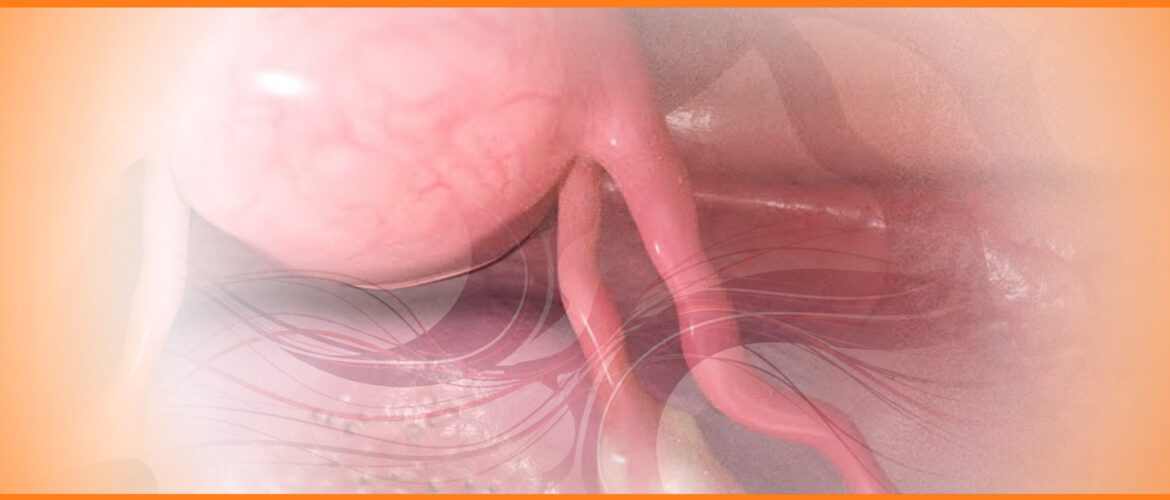

O American College of Obstestricians & Gynecologists (ACOG) publica suas recomendações atualizadas sobre a avaliação clínica, imaginológica e cirúrgica no diagnóstico e manejo da endometriose Foram publicadas em março de 2026 as diretrizes atualizadas do American College of Obstetricians and Gynecologists (ACOG) para o diagnóstico da endometriose. O documento reúne recomendações baseadas em evidências para...